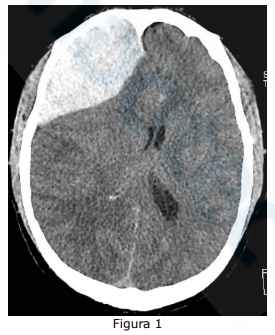

Homem jovem é admitido na emergência de um hospital terciário, vítima de acidente automobilístico (condutor de motocicleta). Ao exame, encontrava-se com pressão arterial 170/100 mmHg, frequência cardíaca de 47 bpm, ritmo respiratório irregular, frequência respiratória de 9 irpm, com saturação de oxigênio 90%. Sem lesões exsanguinantes. Ao exame neurológico, encontrava-se com abertura ocular à dor, emitindo palavras incompreensíveis e com postura de flexão anormal.

Após tomadas as condutas iniciais, ainda assim o paciente evoluiu com anisocoria à direita. Foi realizada tomografia de crânio de urgência, conforme apresentado na Figura 1 abaixo:

Considerando o achado radiológico, o diagnóstico tomográfico é: